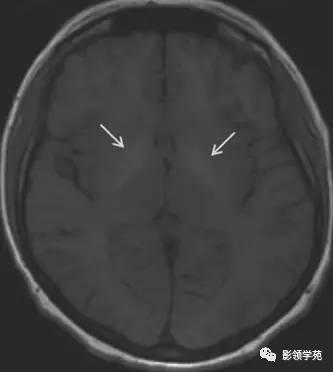

图 6 Fahr 病(钙沉积)患者,显示 T1 尾状核头和壳核高信号

图 7 Wilsion 病(铜沉积)患者显示双侧苍白球高信号(较少见)